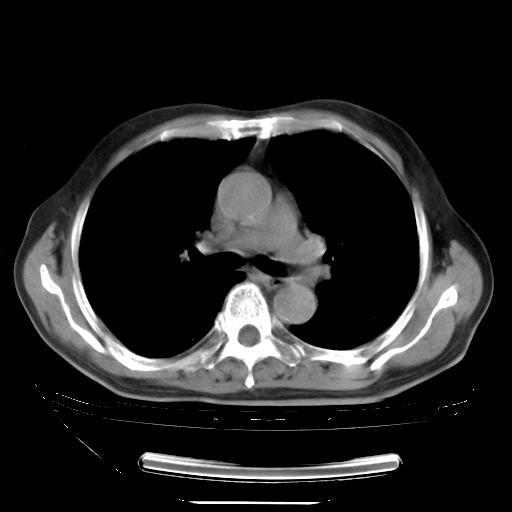

今天复查肺部CT,发现双肺广泛磨玻璃样改变。所以我把3月19日和5月9日相隔50天的肺部CT上传。请大家会诊。

5月9日肺部CT(在4月27日齐鲁医院肺部CT描述部分肺组织磨玻璃样改变,12天后肺组织广泛磨玻璃样改变)

大致读了系列胸部CT:纵隔窗无明显异常,肺窗:从4、27至今:主要是双肺中下野外带可见毛玻璃样改变,目前处于急性肺泡炎阶段,至于原因考虑1、结替组织或胶原血管性疾病所致?2、恶性疾病如恶组在肺部所致的表现或细支气管肺泡癌?3、药物或其它原因如肺蛋白沉着症所致肺泡炎目前不太可能?总之,明天就去请我院的呼吸科、感染科、血液科和临免专家会诊哈。